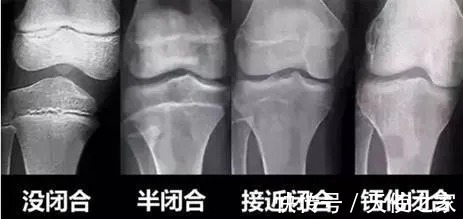

所谓骨骺线就是骨干和骨骺之间的骺软骨,在X光片上显示为一条较宽的透光带。男性一般在20岁前骨骺线闭合,女性一般在18岁前骨骺线闭合。

如果孩子骨骺已经闭合,就意味着身高增长就此停止。想让孩子长高,家长就应抓住骨骺线闭合前那些年。